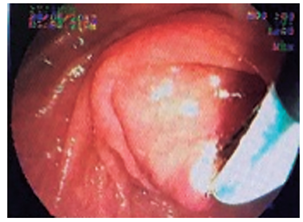

Varón de 76 años, que fue remitido por consultar por dolor intenso en el hipocondrio derecho, de tres días de evolución, malestar general, astenia y adinamia. Al examen estaba adolorido, taquicárdico, taquipneico, afebril, ictérico, con tirajes intercostales, estertores en base derecha y signo de Murphy positivo. Antecedente de diabetes mellitus tipo 2 e hipertensión arterial. Con diagnósticos de neumonía basal derecha, septicemia, trombocitopenia, hipertrofia prostática benigna, insuficiencia renal crónica agudizada, colelitiasis con dilatación de la vía biliar y colédocolitiasis. Durante la ultrasonografía endoscópica, como hallazgo incidental se describe mucosa esofágica negra en su totalidad, recubierta de exudado mucoso, sin erosiones, úlceras ni estrechez, con mucosa por debajo de la línea Z de aspecto usual. La videoendoscopia demuestra ulceración esofágica desde los 21 cm de la arcada dentaria, que se torna circunferencial a los 23 cm, recubierta por fibrina, aspecto negro y grisáceo desde los 27 cm hasta la unión cardioesofágica (Figuras 5, 6 y 7), respetando la mucosa cardial (Figura 8). La colangiopancreatografía retrógrada endoscópica (CPRE) demuestra vía biliar extrahepática dilatada con defecto de llenado en el tercio medio y distal; se practica esfinterotomía pequeña (por trombocitopenia de 31 000 x mm3) (Figura 9) y se extraen cálculos pequeños con balón, dejando un stent plástico de 7 Fr x 7 cm, con drenaje de bilis clara con microcálculos. El paciente evoluciona satisfactoriamente y sale del hospital con resolución del cuadro doloroso e ictérico. A las 10 semanas se encuentra asintomático, sin aceptar la realización de procedimientos de control.